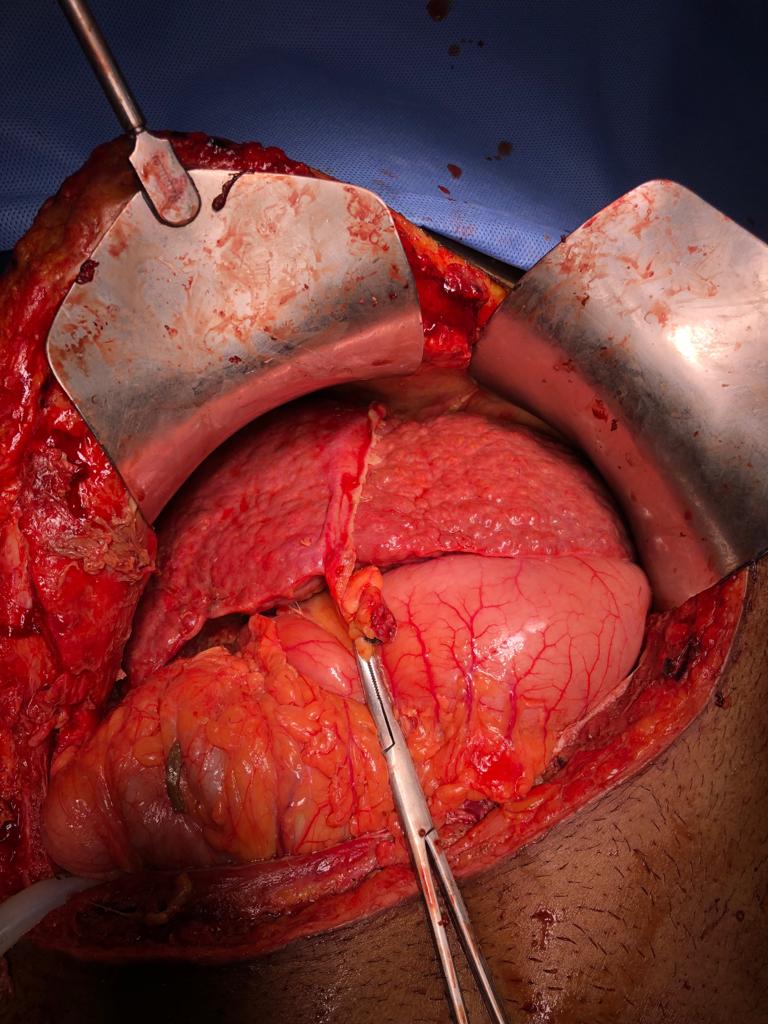

Peritoneal dialysis catheter insertion in patient with polycystic kidney disease

A 59-year-old female with chronic kidney disease stage 5 on dialysis (CKD5D) due to autosomal dominant polycystic kidney disease (ADPKD) was admitted with multiple AV fistula failures and left internal jugular vein permcath related sepsis. In view of thin veins AV fistula creation was not possible. She had central venous stenosis due to multiple dialysis catheter insertions. She needed regular dialysis to survive, but there was no proper site left for placement of dialysis catheter. Peritoneal dialysis option was discussed with the patient. Due to ADPKD she had very large kidneys occupying the majority of the abdominal space. Peritoneal dialysis catheter was inserted in midline with success and nil complications. After 2 weeks of insertion peritoneal dialysis was started and working well. Dr A Kishore Kumar